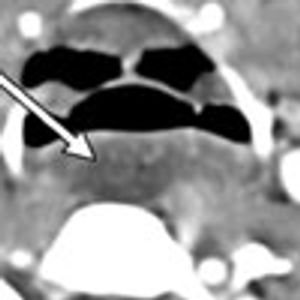

Double aortic arch-a vascular ring anomaly in which both embryonic aortic arches persist and encircle the trachea and esophagus-is rare.